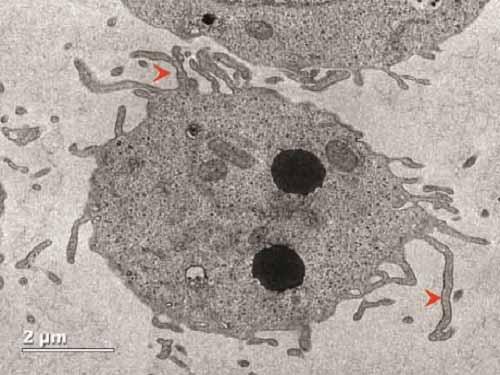

Merzaban and her colleagues revealed one of the functions of this protein by first testing different populations of blood-forming cells for their ability to bind adhesion molecules. They showed that only those cells expressing CD34 could do so, and an unbiased protein screen revealed that CD34 itself was responsible for this binding. Knocking down the protein confirmed CD34's essential role in cell migration.

According to the study's first author, Dina AbuSamra, a former doctoral student in Merzaban's lab now at Harvard Medical School, the results have therapeutic implications beyond simply understanding transplantation. As she points out, the CD34 protein that's found on the surface of leukemic stem cells is different from the one on healthy blood-forming stem cells. There is potential to exploit this difference "to identify leukemic stem cells and, in theory, target them using various approaches," AbuSamra says.

Merzaban also suggests that CD34-negative blood-forming stem cells--a population currently overlooked in transplantation medicine--could be manipulated in ways that boost their binding abilities. Adding these cells to the CD34-positive population might collectively augment overall efficiencies of the procedure, leading to long-term success following transplants. "This is currently a major focus of our lab," Merzaban says.